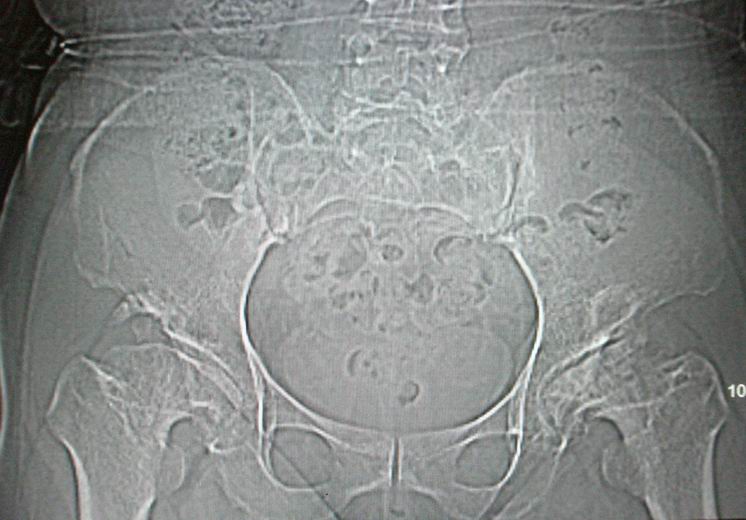

标题: CT12535:女,51岁.双髋痛多年,近加重,左腿难伸直. [打印本页]

标题: CT12535:女,51岁.双髋痛多年,近加重,左腿难伸直.

先天性髋臼发育不良性骨病。双侧股骨头改变为继发性退变。

成人髋臼发育不良性骨关节病.是由于髋臼先天发育不良、髋臼角变大,部分股骨头位于髋臼以外,持重部位少,长期站立、负重造成髋臼退行性骨关节病,主要x线表现是:髋臼变浅平,髋臼角增大,ce角小于30度,髋关节骨性关节面增生硬化,关节间隙变窄,髋臼及股骨头可有囊变.但股骨头变形轻微,与股骨头坏死相比,预后好,可两三年变化不大,而股骨头坏死早期关节间隙不窄或增宽,等到间隙变窄时股骨头已明显变形.

鉴别:股骨头缺血坏死

髋关节创伤性骨关节炎